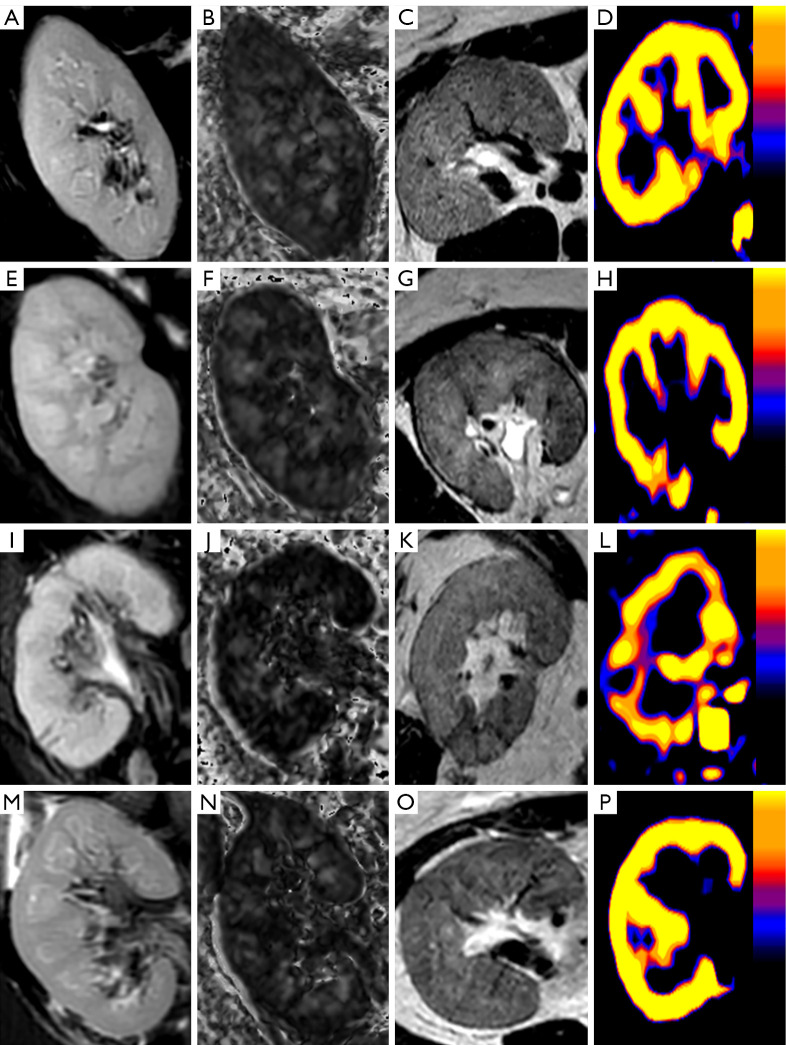

Methods: A total of 86 subjects were enrolled in the study, of whom, 20 had stable renal function, and 66 had biopsy-confirmed CAD. Imaging was performed on a 1.5-T MRI system using T2-weighted imaging, arterial spin labeling (ASL), and diffusion tensor imaging (DTI). The serum creatinine, estimated glomerular filtration rate (eGFR), 24-hour urinary protein (24hUP), renal blood flow (RBF), and fractional anisotropy (FA) values of the subjects were measured. Correlation analysis was applied to assess MRI parameters' association with eGFR, while receiver operating characteristic (ROC) curves were used to evaluate the diagnostic efficacy of fMRI parameters and clinical parameters for CAD.

Results: The subjects were categorized into CAD groups based on their eGFR levels. The control group had higher renal RBF [277.69±67.17 vs. 138.60 (99.54-193.51)] and FA values [cortex: 0.16 (0.14-0.16) vs. 0.13 (0.11-0.16); medulla: 0.32±0.06 vs. 0.24 (0.20-0.29)] than the CAD group (P<0.01). Cortical RBF decreased progressively across the CAD subgroups [group 1 (mild: 213.33±67.07) > group 2 (moderate: 151.14±53.21) > group 3 (severe: 92.89±35.62); all P<0.05]. Similarly, there was a gradual decrease in medullary FA across the CAD subgroups [group 1: 0.29±0.04; group 2: 0.24 (0.19-0.29); group 3: 0.20±0.06]. However, no statistically significant difference was found in medullary FA between groups 2 and 3 (P=0.102). The correlation analysis showed that cortical RBF and medullary FA were positively correlated with the eGFR in the CAD group (r=0.604, P<0.001; r=0.574, P<0.001). The combined RBF, medullary FA, 24hUP, and eGFR model (RBF-FA-24hUP-eGFR) had an area under the curve (AUC) of 0.95 [95% confidence interval (CI): 0.91-1.00], which was significantly better than the AUCs of the single indicators of 24hUP and medullary FA (AUC =0.78, 95% CI: 0.68-0.88; AUC =0.79, 95% CI: 0.69-0.89, P<0.05). Further, the combined RBF, medullary FA, and, 24hUP model (RBF-FA-24hUP) was significantly superior to single 24hUP in differentiating among the subgroups (all P<0.05). In the CAD subgroups, while the performance of RBF on its own was close to that of the RBF-FA-24hUP model, the AUC of the combined model showed an increasing trend compared with RBF. Notably, the RBF-FA-24hUP model (AUC =0.86, 95% CI: 0.76-0.97; P<0.001) also surpassed medullary FA alone (AUC =0.69, 95% CI: 0.54-0.85; P=0.023) in distinguishing between the subjects in group 2 and group 3 (P<0.05).